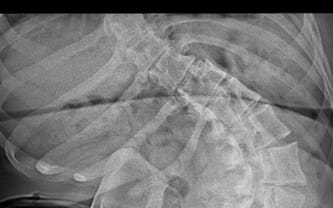

Dziecięce porażenie mózgowe czterokończynowe